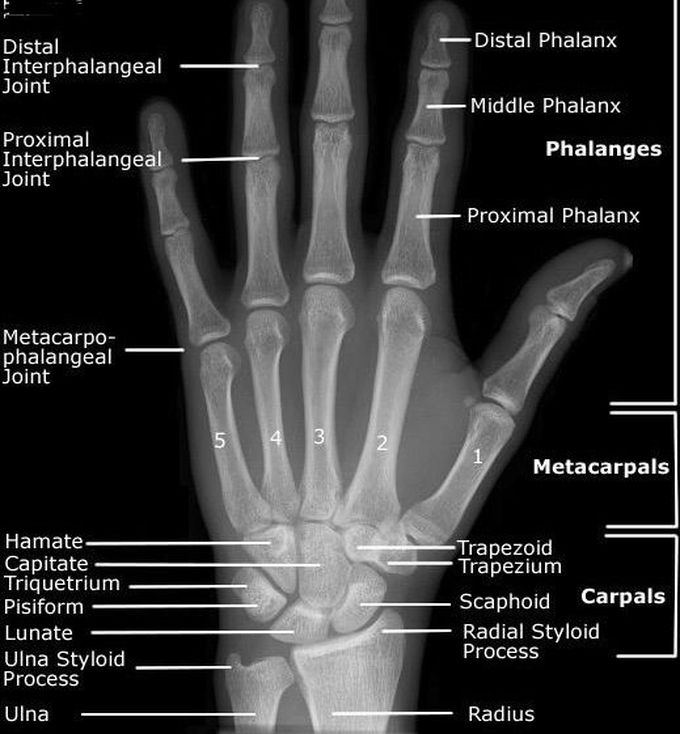

Normal X-ray for hand

Medicine

Radiology